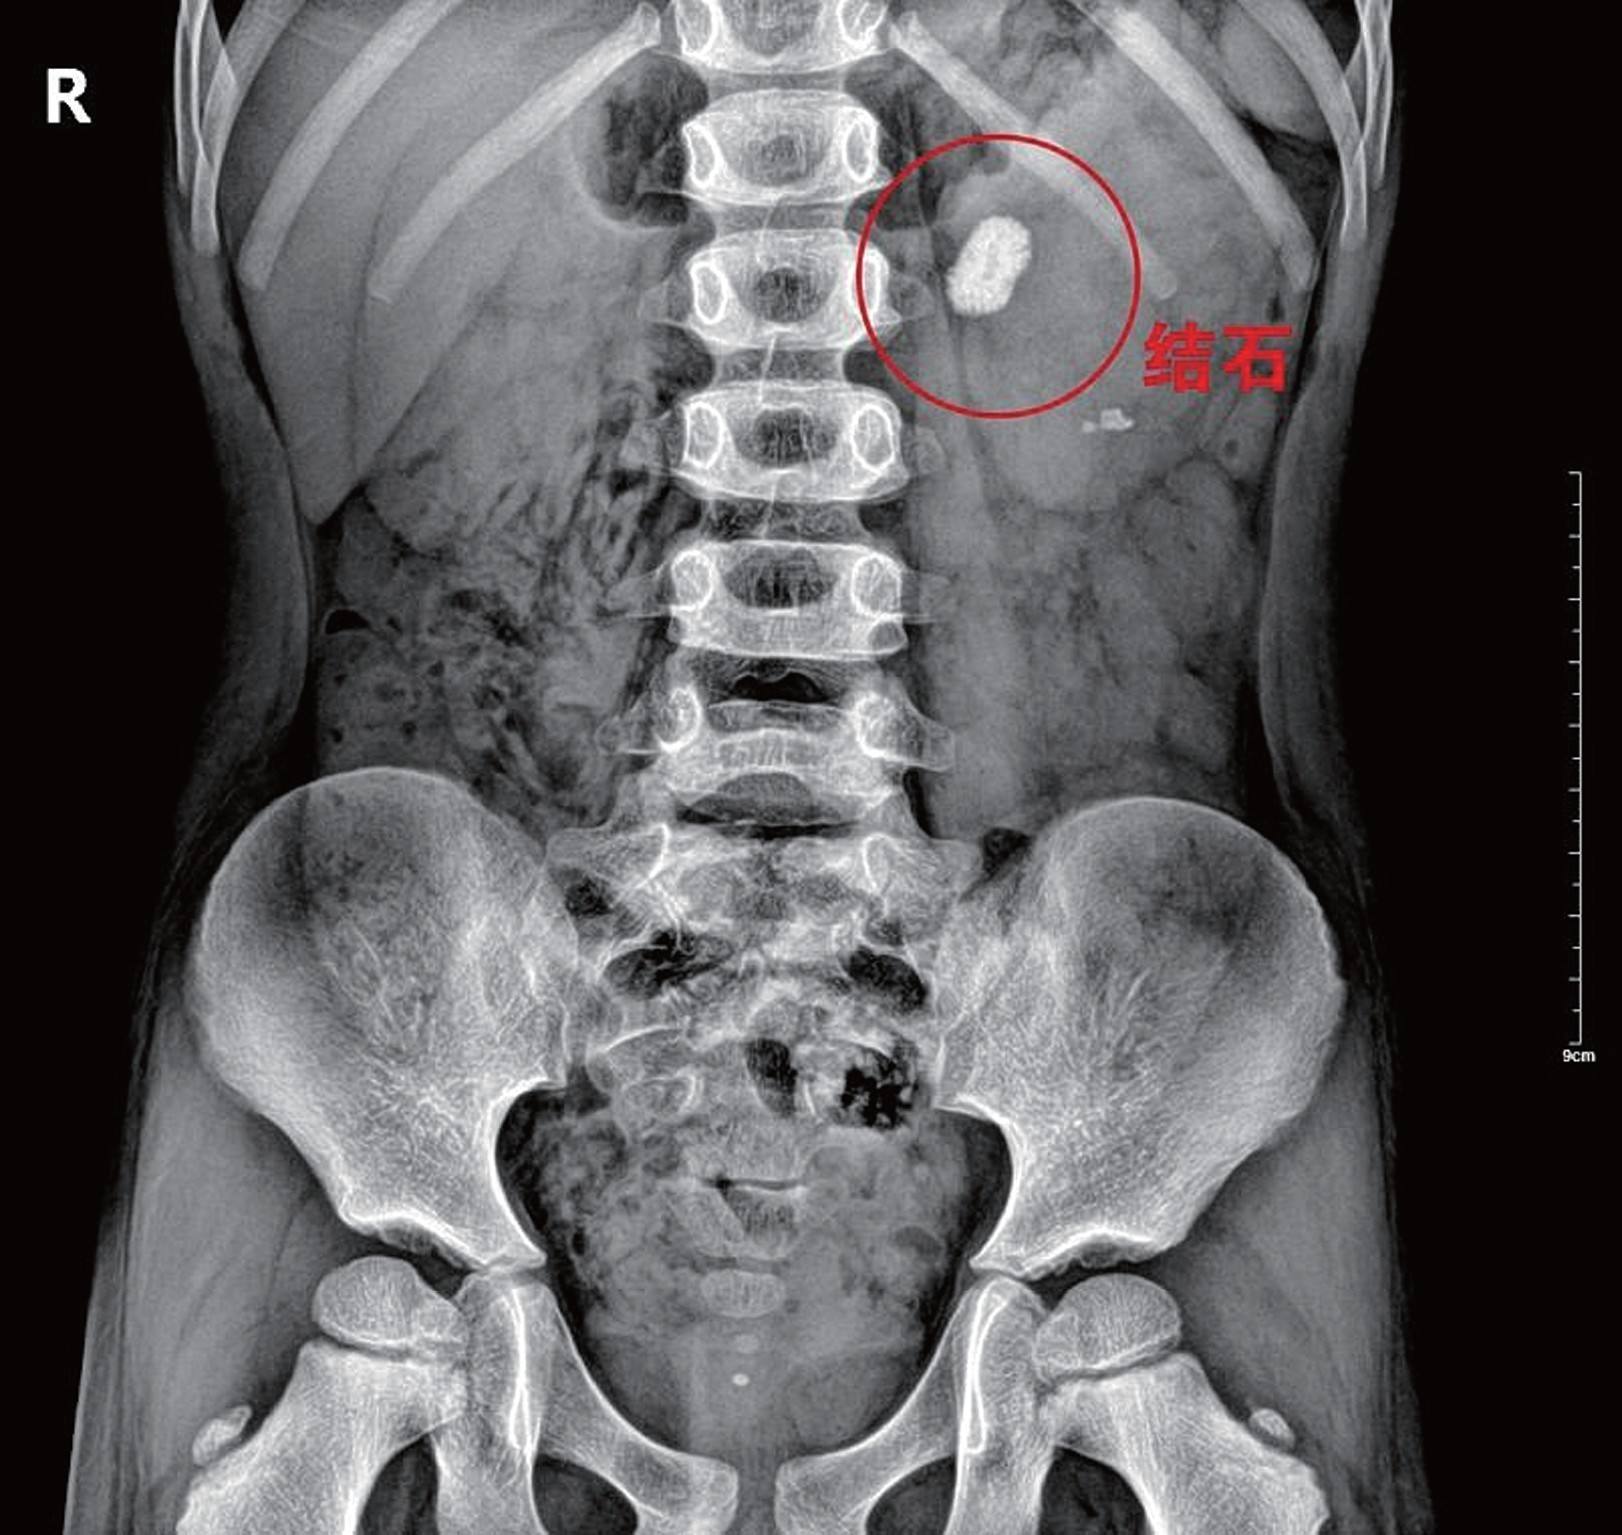

3、尿结石

文章开头我们说的那个小女孩主要是因为体内摄入过多钙质,身体无法完全吸收,剩余的钙质又无法正常排出体外,于是就在体内形成了结石,大家都知道结石疼起来是非常痛的,严重的都是要通过手术取出,为了少让孩子受罪,家长们还是得多留心啊!